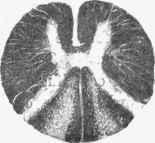

The posterior columns are the parts affected, but the disease does not invade these columns uniformly. Its special seat is the outer parts of the posterior columns, namely, the Posterior root-zones, or columns of Burdach, and it is stated that these alone are affected in the earlier stages (see Fig. 315). The Columns of G-oll are secondarily invaded, as the result of an ascending sclerosis. That this is so appears from the actual examination of the cord at various levels. The disease begins, and is usually most advanced, in the lumbar region, but in the lowest part of that region the lateral parts of the posterior columns may be alone involved. On passing upwards the columns of Goll become also affected, so that in the upper half of the lumbar swelling the degeneration may be co-extensive with the posterior columns. This continues in the dorsal region, but in the cervical the sclerosis begins to diminish externally, and shades off into the columns of Goll, in which it may be continued up into the restiform body. The actual primary lesion is therefore that in the external parts of the posterior columns, and the affection in the columns of Goll is really an ascending secondary degeneration, these columns being, as already stated, the principal seat of ascending sclerosis. It is to be noted, however, that the direct cerebellar tract and the antero-lateral tracts are not affected.

Fig. 315. - Cord in early stage of locomotor ataxia. The columns of Goll are unaffected, but the posterior root-zones are in a state of sclerosis.